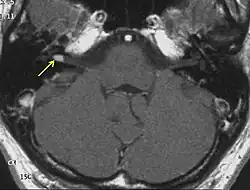

Eine sichere Diagnose liefert nur die histologische Untersuchung nach einer Gewebeentnahme. Erstmals röntgenographisch dargestellt wurden Akustikusneurinome mit Erweiterungen des inneren Gehörgangs durch Salomon Eberhard Henschen (1910) und Hendrik Willem Stenvers (1917).[4] Klinisch relevante Tumoren können heute mit einer Magnetresonanztomographie (MRT) zuverlässig detektiert werden.

Bei Schwindel werden zunächst akute Infektionen ausgeschlossen, die ähnliche Krankheitsbilder ergeben. Eine auffällige Hörminderung wird durch ein Tonaudiogramm festgestellt. Danach wird eine Messung der frühen akustisch evozierten Potenziale (FAEP) durchgeführt, vor allem, wenn eine seitendifferente oder einseitige Schallempfindungsschwerhörigkeit vorliegt. Bei der Messung der FAEP zeigt sich ein Akustikusneurinom in der Laufzeiterhöhung der Signale vom Innenohr zum Stammhirn. Das liegt daran, dass durch das AKN die Myelinscheide der Nervenbahn beschädigt ist und die elektrischen Impulse nur noch unter Verlusten transportiert werden können. Bei deutlich seitendifferentem Kurvenbild bzw. seitendifferenten Laufzeitunterschieden der Potentiale sollte eine Magnetresonanztomographie des Schädels mit und ohne Kontrastmittel durchgeführt werden, um mit ausreichender Sicherheit ein Akustikusneurinom ausschließen zu können.